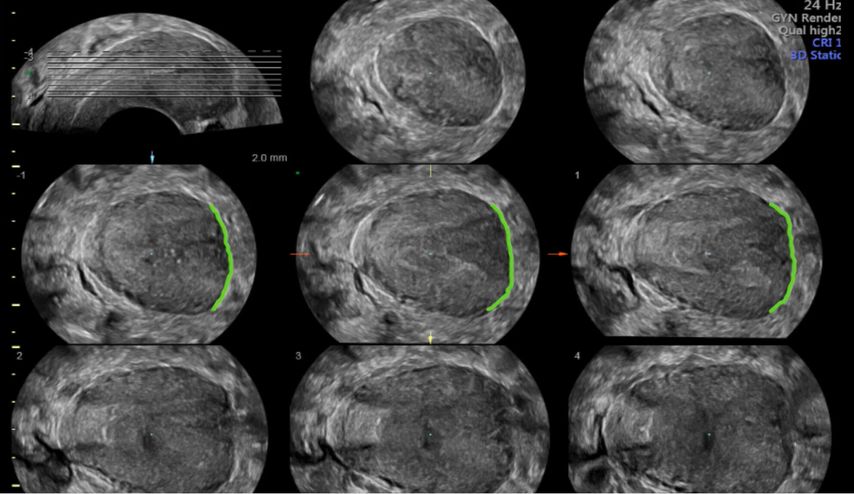

Ein weiterer Modus, «tomographic ultrasound imaging» (TUI) oder «multi-view», erlaubt die Darstellung mehrerer paralleler Schichten (bzw. multiplanarer Rekonstruktionen) in einem Raster. Dies ermöglicht, zusätzliche Details in bestimmen Bildabschnitten zu erhalten.

In unklaren Fällen, in denen die äussere Uteruskontur in der MPR nicht eindeutig zu sehen ist und so die Unterscheidung zwischen einem Uterus (sub-)septus und einem Uterus bicornis schwierig ist, hilft TUI bei der Differenzialdiagnose (Abb. 5 und 6).

Abb. 5: «Tomographic ultrasound imaging» (TUI). In mehreren parallelen Ebenen kann die äussere Uteruskontur analysiert werden (konvex vs. konkav)